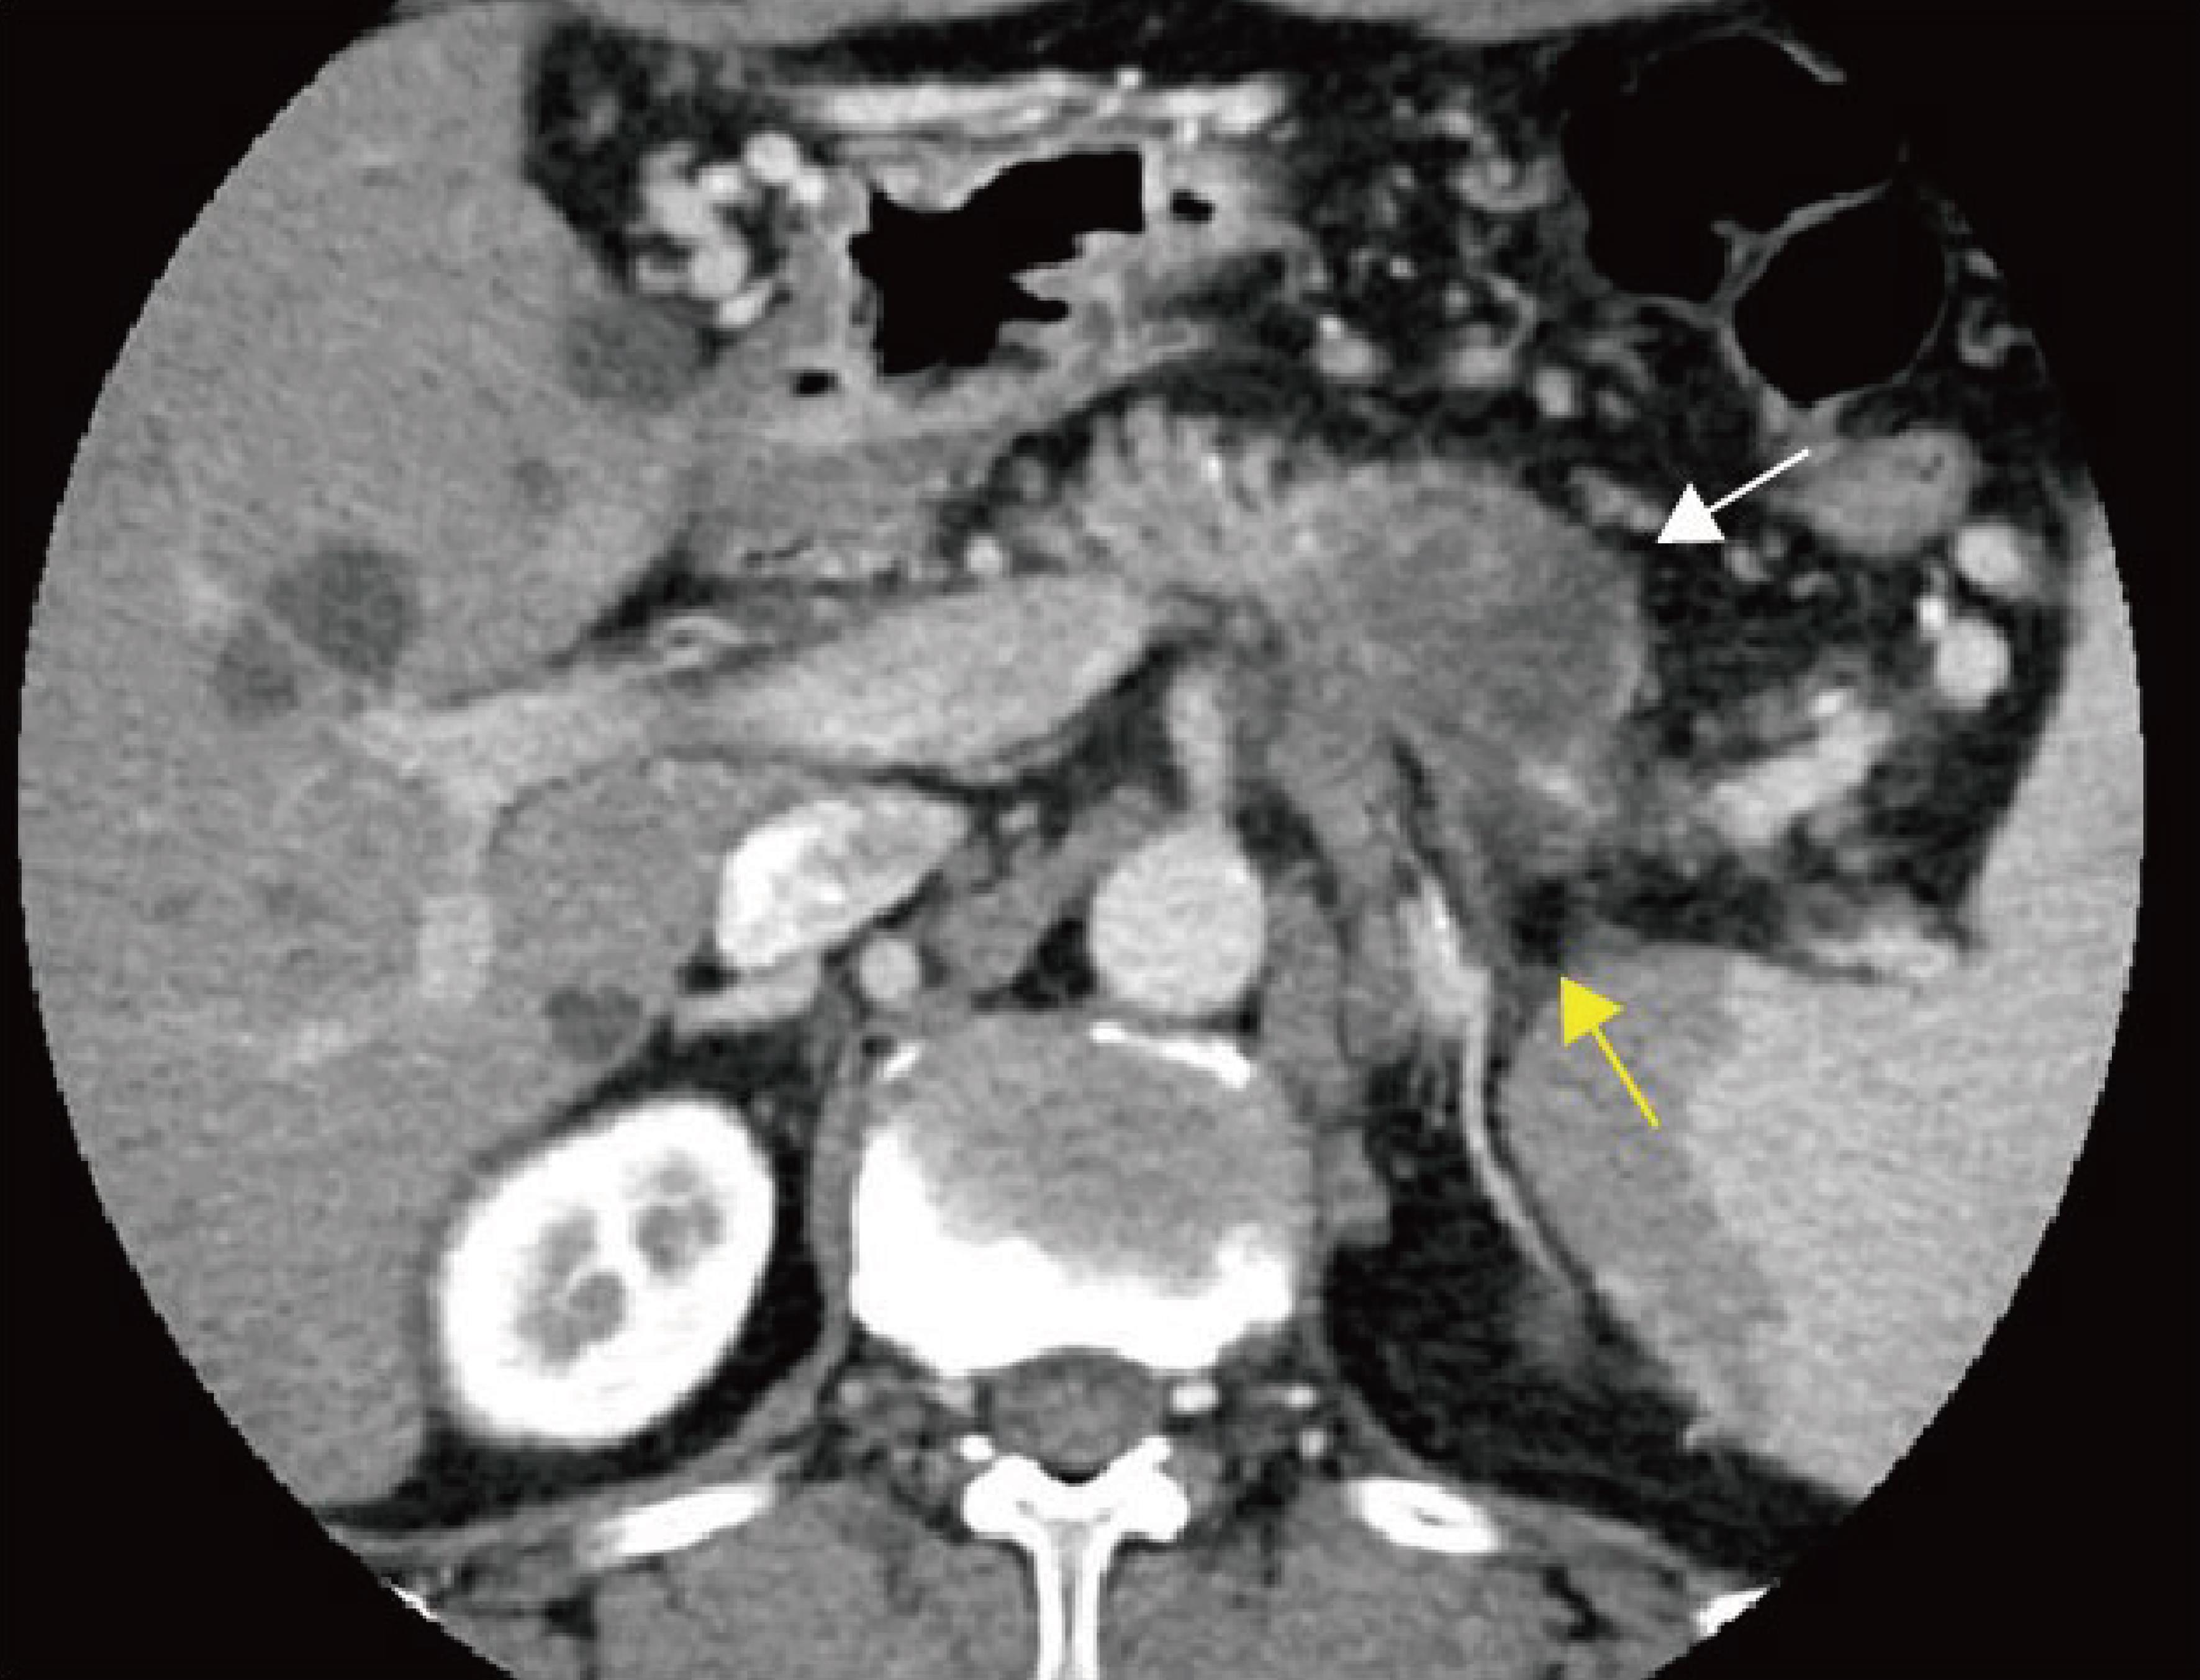

Explanation: Approximately 13–23% of pancreatic cancer patients are found intraoperatively to have hepatic or peritoneal metastases, rendering the tumor unresectable.130 Although multiphasic helical CT with volumetric scanning has improved detection rates of metastatic lesions, contrast-enhanced CT sensitivity for hepatic metastases remains suboptimal (38–76%).131 MRI with DWI demonstrates high sensitivity (86–97%) for detecting focal hepatic lesions, including subcentimeter metastases (sensitivity 60–91%).132–134 Meta-analyses indicate that MRI outperforms CT in overall diagnostic accuracy for hepatic metastases in pancreatic cancer, with pooled sensitivity higher for MRI than CT (85% vs. 75%), while pooled specificity is comparable (98% vs. 94%).135 Another meta-analysis similarly found comparable specificity between CT and MRI (94% vs. 96%) but superior sensitivity for MRI (83% vs. 45%) in diagnosing hepatic metastases.136 Peritoneal metastases from pancreatic cancer typically manifest as miliary nodules on the omentum and mesentery, irregular peritoneal thickening, and small-volume ascites, all suggestive of peritoneal carcinomatosis or implantation (Fig. 12).137 CT sensitivity for peritoneal metastases depends on lesion size; Archer et al.138 reported sensitivity of only 25% for lesions <0.5 cm, increasing to 90% for lesions >5 cm. MRI, including DWI sequences, is a sensitive imaging modality for detecting peritoneal metastases.139 Studies suggest that combining high b-value (b = 800 s/mm2) DWI with conventional MRI improves preoperative detection sensitivity (from 0.58 to 0.85) and accuracy (from 0.67 to 0.85) for peritoneal tumors compared to conventional MRI alone.140

Evaluation of hepatic and distant metastases in pancreatic cancer.

Fig. 12  Evaluation of hepatic and distant metastases in pancreatic cancer.

a, b Same patient. (a) Axial portal venous–phase T1-weighted MRI showing a hypointense mass in the pancreatic body and tail (white arrow). (b) Axial portal venous–phase T1-weighted MRI showing multiple ring-enhancing lesions in the liver (yellow arrows), consistent with hepatic metastases. c, d Same patient. (c) Axial portal venous–phase CT showing a hypodense mass in the pancreatic body and tail (white arrow). (d) Axial portal venous–phase CT showing nodular changes of the omentum (yellow arrow), consistent with omental metastases. CT, computed tomography; MRI, magnetic resonance imaging.